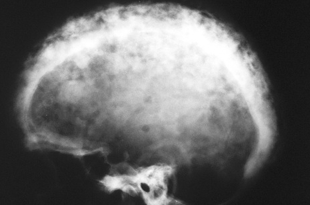

paget’s disease of bone